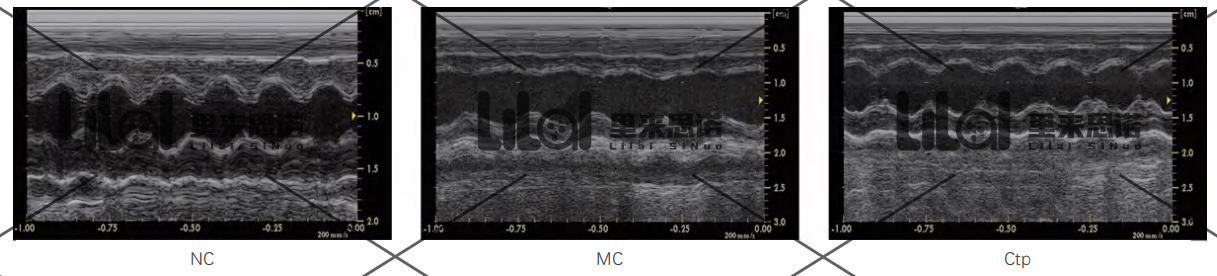

心功能檢測:實驗結束后進行心臟超聲,檢測各組大鼠的心功能。結果發(fā)現(xiàn):與NC組相比,MC組大鼠左室射血分數(LVEF)和左室短軸縮短率

(LVFS)顯著降低;而Ctp能顯著提高心衰大鼠LVEF和LVFS,改善心衰大鼠心功能(p<0.01)。